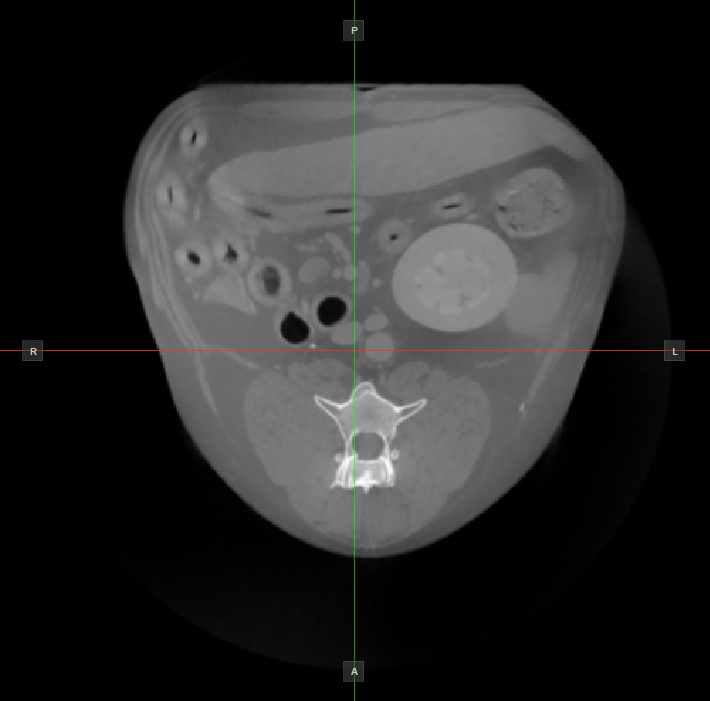

Az aktív nézetablakban nem látható másik két kép síkjának helyzetét és metszését két függőleges és vízszintes vonal jelzi, amelyeket szeletelőknek nevezünk. Minden szeletelő végpontját egy betű jelöli, amely a 3D térfogat megfelelő irányának/oldalának felel meg az RAS koordinátarendszer alapján.

Az elérhető hat oldalból csak négy van jelölve minden 2D nézetablakon. A címkék és a hozzájuk tartozó oldalak a következők:

Beteg jobb oldala (R), a test jobb oldalát jelöli

Beteg bal oldala (L), a test bal oldalát jelöli

Elülső (A), a test elülső oldalát jelöli

Hátsó (P), a test hátsó oldalát jelöli

Felső (S), a test felső oldalát jelöli

Alsó (I), a test alsó oldalát jelöli